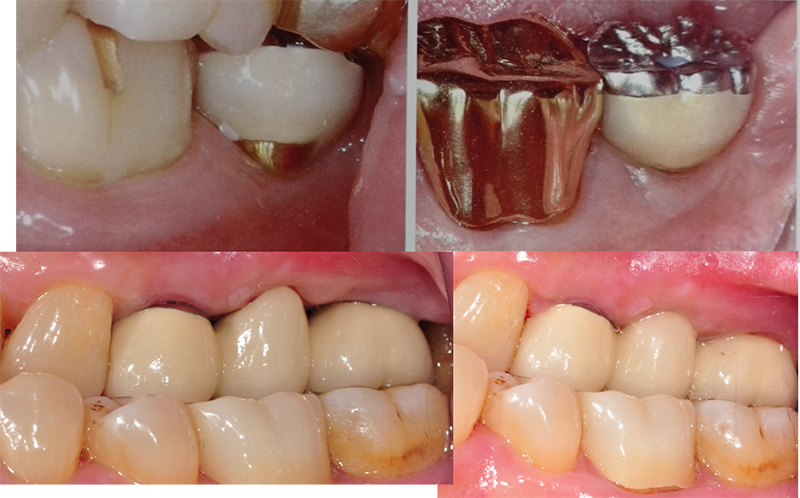

2. Emergence profile À» ¸¸µå´Â µ¥ ÃÖ°í

±×·¡¼ ÀüÄ¡ºÎ¿¡¼´Â ÇöÀç °ÅÀÇ ÀÌ ÀÓÇöõÆ®(Astra type implant)¸¦ ¾²°í ÀÖ´Ù.

Fixture topÀÌ ITI¿Í´Â ´Ù¸£°Ô bone levelÀ̶ó¼, pink esthetics(ÀÕ¸öÀÇ ½É¹Ì)À» ±¸ÇöÇϱâ

À§ÇÑ ÀÕ¸öÀÇ µÎ²²¸¦ ´Ù¾çÇÏ°Ô È®º¸ÇÒ

¼ö ÀÖ´Ù.

Emergence profileÀ» ±¸ÇöÇϱâ À§Çؼ´Â ÃæºÐÇÑ µÎ²²ÀÇ ÀÕ¸öÀÌ ÇÊ¿äÇÏ´Ù.

º¯¿¬°ñÀÌ ¾ÈÁ¤µÇ±â

¶§¹®¿¡ ±¸ÇöÇÑ ÀüÄ¡ºÎÀÇ ½É¹ÌÀû »óŸ¦ °è¼Ó À¯ÁöÇÒ ¼ö ÀÖ´Ù.

Fixture top placement, Abutment selection, Margin placement, &

Sub-gingival contour of

crown¸¦ ÃÑüÀûÀ¸·Î °í·ÁÇØ¾ß ÀüÄ¡ºÎ EstheticsÀ» ±¸ÇöÇÒ ¼ö ÀÖ´Ù.

Emergence profileÀº ÀüÄ¡ºÎ

½É¹Ì»Ó¸¸ ¾Æ´Ï¶ó ±¸Ä¡ºÎ¿¡¼´Â ¡®À½½Ä¹° Àú·ù¡¯¸¦ ¸·´Â´Ù.

Sub-gingival contour ±îÁö ±¸ÇöÇØ ³»¾ß ÁøÂ¥ emergence profileÀÌ´Ù.